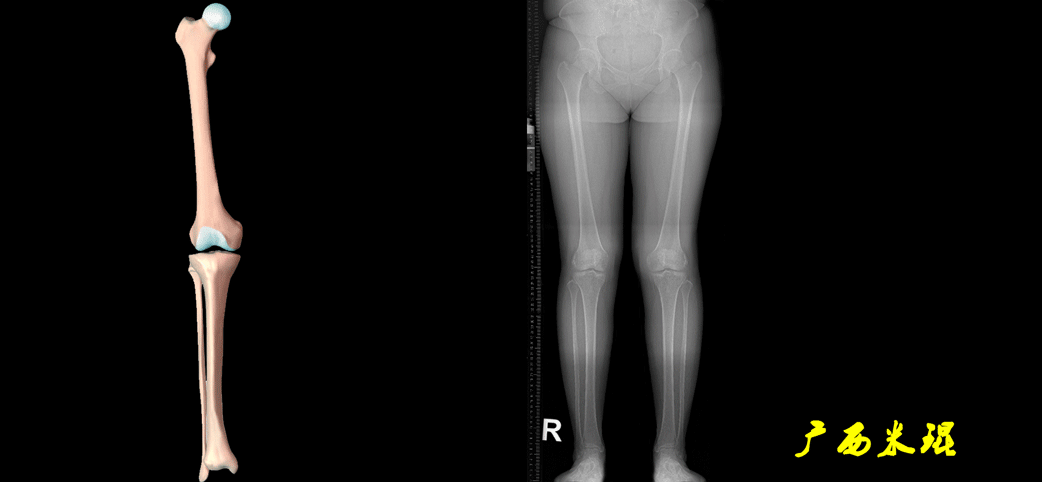

下肢力线及相关角度测量的前提是必须拍摄标准的站立位也就是负重位的下肢全长片。目前这样的照片都是放射科的技师在电脑上拼接出来的,大部分医院的DR都能够做到这一点。

患者直立于摄影架上,后背贴近摄影架,双手自然下垂,膝关节尽量伸直,足部与双肩同宽,要求投照时双髌骨朝正前方,通常患者双足尖应平行向前即可。

提醒一下大家,拍摄过程中应避免下肢的外旋和内旋。如果有一侧肢体短缩时,投照应当用脚垫垫高短缩肢体,使骨盆保持水平,这样下肢短缩测量才精确。如果有肢体旋转畸形时,还是以髌骨朝前为标准,虽然此时双足可能不能保持平行。

无论如何,拍摄出来的下肢全长片必须包含髋关节中心、膝关节中心及踝关节中心,否则对临床是无用的。有了一张下肢的全长照片,我们需要确定下肢关节的中心点,通过中心点画出下肢的各种轴线,然后利用轴线与关节线的相交得出各种所需要的角度。